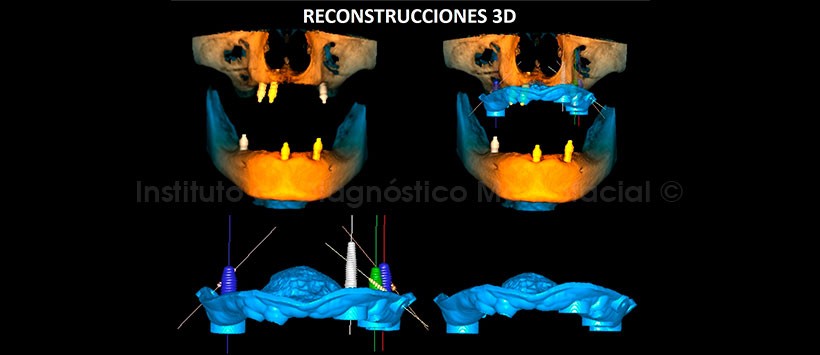

En la tomografía computarizada de haz cónico (TCHC), se realiza la planificación virtual de colocación de cuatro implantes dentales en zonas de piezas 17, 23, 26 y 27 (Figura 2, 3), y sobre la planificación se realiza la confección virtual de la guía quirúrgica (Figura 4). En la reconstrucción 3D (Figuras 5) se aprecia con detalle la orientación y la disposición final de los implantes dentales a ser colocados, además se observa la guía quirúrgica confeccionada virtualmente que posteriormente fue impresa físicamente para su utilización en el procedimiento quirúrgico (Figura 6).